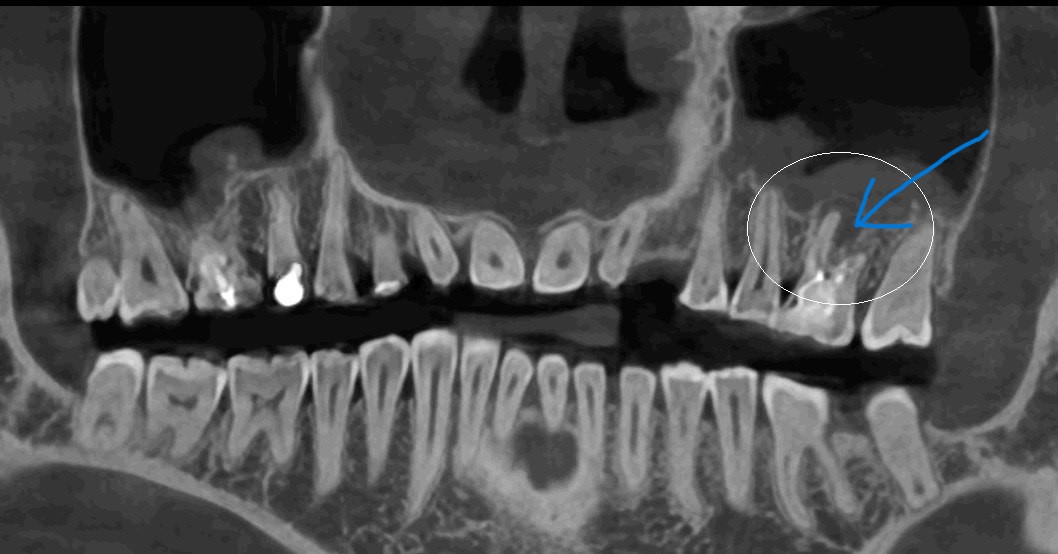

На снимке врач видит примерно такую картинку: чёрное облачко вокруг корня — это и есть периодонтит

Хронический апикальный периодонтит редко кто приходит лечить специально. Чаще всего его обнаруживают случайно: стоматолог делает рентген, а там — чёрное облачко вокруг корня зуба. Вот так он и выглядит.

По ОМС такой зуб скорее всего удалят, но не потому, что врачи плохие. Просто, чтобы перелечить уже пролеченные каналы и оставить зуб на месте, нужна современная техника, те же микроскопы и увеличительная техника, а в государственных клиниках это нечастая история. Поэтому, как правило, предложат удаление. Хотя есть шансы зуб сохранить. Но и в клиниках подороже далеко не каждый терапевт возьмётся за такую работу — она тонкая и сложная.